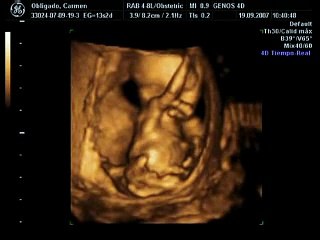

الاسبوع الثالث والثلاثون من الحمل: اكملي كل التحضيرات وحاولي الاسترخاء

يطرأ ابتداءً من هذا الأسبوع المزيد من التغيّرات على جسمك فيتوسّع رحمك ليتجاوز السرة لكنه يبقى تحت منطقة الثديين.